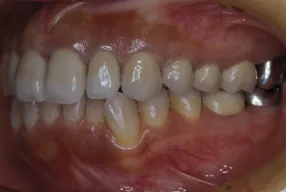

初診時

治療完了時

| 患者様のお悩み | 咀嚼障害、左の奥歯が抜けた。 |

| 治療法・使用素材 | インプラント治療の後、セラミック治療 |

| 患者様の年代 | 60代 |

| 治療開始年齢 | 60代 |

| 治療にかかった期間 | 1年6か月 |

| 性別 | 男性 |

| この治療のリスクについて | 歯ぎしりがひどいので修復物の耐久性が将来的に問題になる可能性があること |

| 治療にかかった費用 | 450万円 |